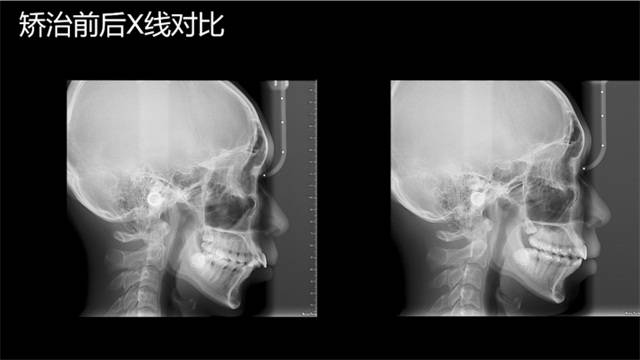

正畸医生揭秘丨0成本,只需几个动作就能改善嘴突的方法,真行吗

嘴巴前突,一般是由牙齿前突造成的。而牙齿前突又可以分为牙性和骨性。嘴突在临床最常见的有双颌前突或者下颌后缩(显得上颌前突)。

双颌前突的患者常表现为上下前牙向嘴唇方向倾斜,自然放松状态下开唇露齿,闭唇困难,闭唇时颏部肌肉紧张,面下部的轮廓线条不自然。双颌前突又可以分为骨性前突和牙(牙槽骨)性前突,也就是我们常说的嘴突和牙突。

如果是牙齿问题需要到医院进行牙齿矫正,后期配合牙套和舌肌训练,坚持正确使用能明显改善突嘴。但如果是骨骼问题,则建议去医院拍个片子检查,通过手术才能真正改善突嘴的问题。